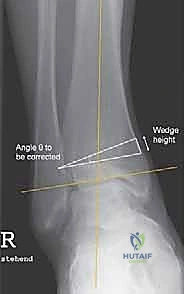

- الأشعة السينية أثناء الوقوف (Weight-Bearing X-rays): هذه هي الخطوة الأهم. لا يمكن تقييم تشوه الكاحل بدقة والمريض مستلقٍ. يجب أخذ صور أشعة طويلة للساقين بالكامل لتحديد "محور التحميل الميكانيكي" وقياس زوايا التشوه بدقة متناهية (مثل زاوية TAS وزاوية TLS).

النجاح في عملية قطع العظم فوق الكاحل لا يحدث بالصدفة، بل هو نتيجة تخطيط هندسي وبيوميكانيكي دقيق قبل دخول غرفة العمليات. يقوم الدكتور محمد هطيف باستخدام برامج كمبيوتر متخصصة لتحليل صور الأشعة الخاصة بالمريض. يتم حساب الزوايا بدقة تصل إلى كسور الدرجة، وتحديد مكان القص الجراحي (Osteotomy site) بشكل مثالي.

- قص العظم (Osteotomy): باستخدام منشار جراحي دقيق وموجهات خاصة، يتم قص عظم الظنبوب (وفي بعض الأحيان عظم الشظية أيضاً) بالزاوية التي تم تحديدها مسبقاً في التخطيط الثلاثي الأبعاد.

- تصحيح المحور: يتم فتح أو إغلاق الشق العظمي للوصول إلى المحور الميكانيكي السليم للكاحل. يتم التحقق من ذلك داخل غرفة العمليات باستخدام جهاز الأشعة السينية الفلوروسكوبي (C-arm).